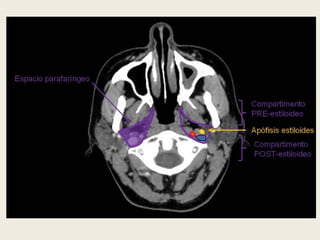

ESPACIO PARAFARÍNGEO (O ESPACIO

PARAFARÍNGEO PREESTILOIDEO)

 Es un área de tejido graso y localización central en la fascia

cervical profunda, que incluye ramificaciones de la tercera

rama del trigémino (V3), las arterias maxilar y faríngea

ascendente, el plexo venoso faríngeo y glándulas salivares

accesorias.

 En relación con el espacio parafaríngeo preestiloideo es

importante remarcar que la fascia del músculo pterigoideo

medial y el tensor del velo del paladar tienen una inserción

común en el borde medial del foramen oval.

 Este espacio puede ser asiento de tumores de glándulas

salivares accesorias y cuando es invadido por otras lesiones,

éstas tienen una vía de acceso libre hacia los espacios

submandibular y sublingual, ya que éstos se comunican entre

sí.